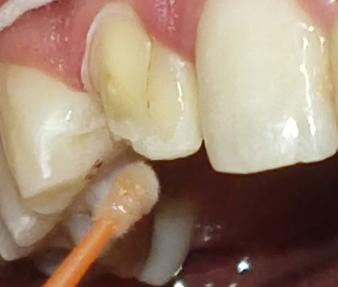

Al examen clínico intraoral se evidenció en la pieza, motivo de consulta, una alteración del desarrollo

dentario de forma, asemejando tener dos coronas en una sola pieza dentaria, unidas parcialmente en el tercio medio y cervical, delimitado por un surco central proveniente de la unión cementoesmalte, presentando una corona disto vestibular y otra mesiopalatina, hacia el borde incisal las coronas están separadas, también se evidencia a nivel del surco una caries de esmalte con cambio de coloración marrón (Fig. 1.A). A nivel de la cara palatina de la pieza 1.2 se evidencia la presencia de una cúspide accesoria en la corona mesiopalatina la misma que se denomina cúspide en garra (Fig. 1.B).

Figura Nº1 A. Fotografía intraoral en oclusión, señalando la pieza (1.2) note el surco vestibular con cambio de coloración. B. Fotografía intraoral oclusal se observa en la corona mesiopalatina la cúspide en garra.

Fuente: Elaboración propia, octubre 2021.